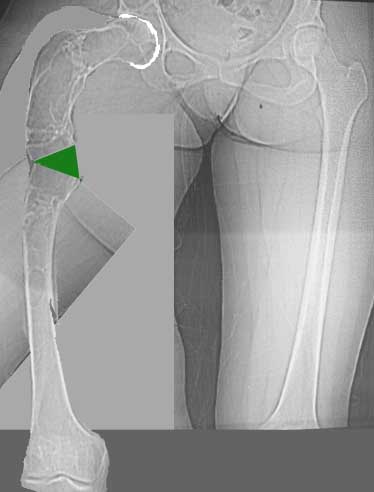

Женщина 28 лет, Больна с 12 летнего возраста, Когда после адекватной травмы получила перелом бедра. На рентгенограммах выявлено какое-то (рентгенограмм и документов нет) изменение бедренной кости, была оперирована, имеется гистологическое заключение - фиброзная дисплазия.дСформировалась деформация бедра. На сегодня - Укорочение 7см. Грубая деформация бедра по типу "пастушьей палки", последний патологический перелом в январе 2004г., консолидировавшийся при консервативном лечении. Имеются грубые изменения и в надвертлужном массиве.-- С уважением, Leonid

Возможна аппаратная коррекция оси с формированием клиновидного регенерата, которая решила бы и проблему укорочения (что, впрочем, нужно уточнить по схеме, сделанной по рентгенограмме с хорошим захватом смежных суставов - схемка по присланному снимку в приложении). По окончании коррекции - блокируемый стержень, который и сократит время пребывания в аппарате, и вообще возврата к нормальной жизни, а также будет мерой профилактики патологических переломов.

Na zglad', niobhodimo delat' skagrammu niznih konechnostei s zahvatom niznih odelov pozvonochnika, taza, i vseh sustavov ninih konechnoste,

Za tem, odnomomentno sdelat':

Exterpasio polosty nadacetalumom, i zopolnit' ee kostnim sementom:

Korreksija deformasii bedra Hibridnim apparatom, s odnovremennim udleneniem bedra

Собственно сустав не беспокоит, объем движений полный. По скиаграммам получается, что достаточно одной остеотомии на вершине деформации, чтобы восстановить длину и вывести коленный сустав в нужное положение.

Т.к. укорочение 7 см, то начинать будем с соеотомии и коррекции аппаратом. Спасибо

Подобная дефомация может быть исправлена только при помощи КДО аппаратов с клиновивной резекцией бедренной кости + исправление ротационного компонента.

Т\б сустав явно патологичен. Но лечение патологии т\б сутава можно оставить на будущее.

первостепенно- исправление оси. Ото главное в травме.

Моё мнение, что двойная остеотомия бедра с аппаратом Илизарова + Гексаподный механизм, или Тэйлора, В данной ситуации является методом выбора. Я очень извеняюсь за качество прилагаемых снимков, в которых я постарался отразить разницу междe одной и двумя остеотомиями бедра.